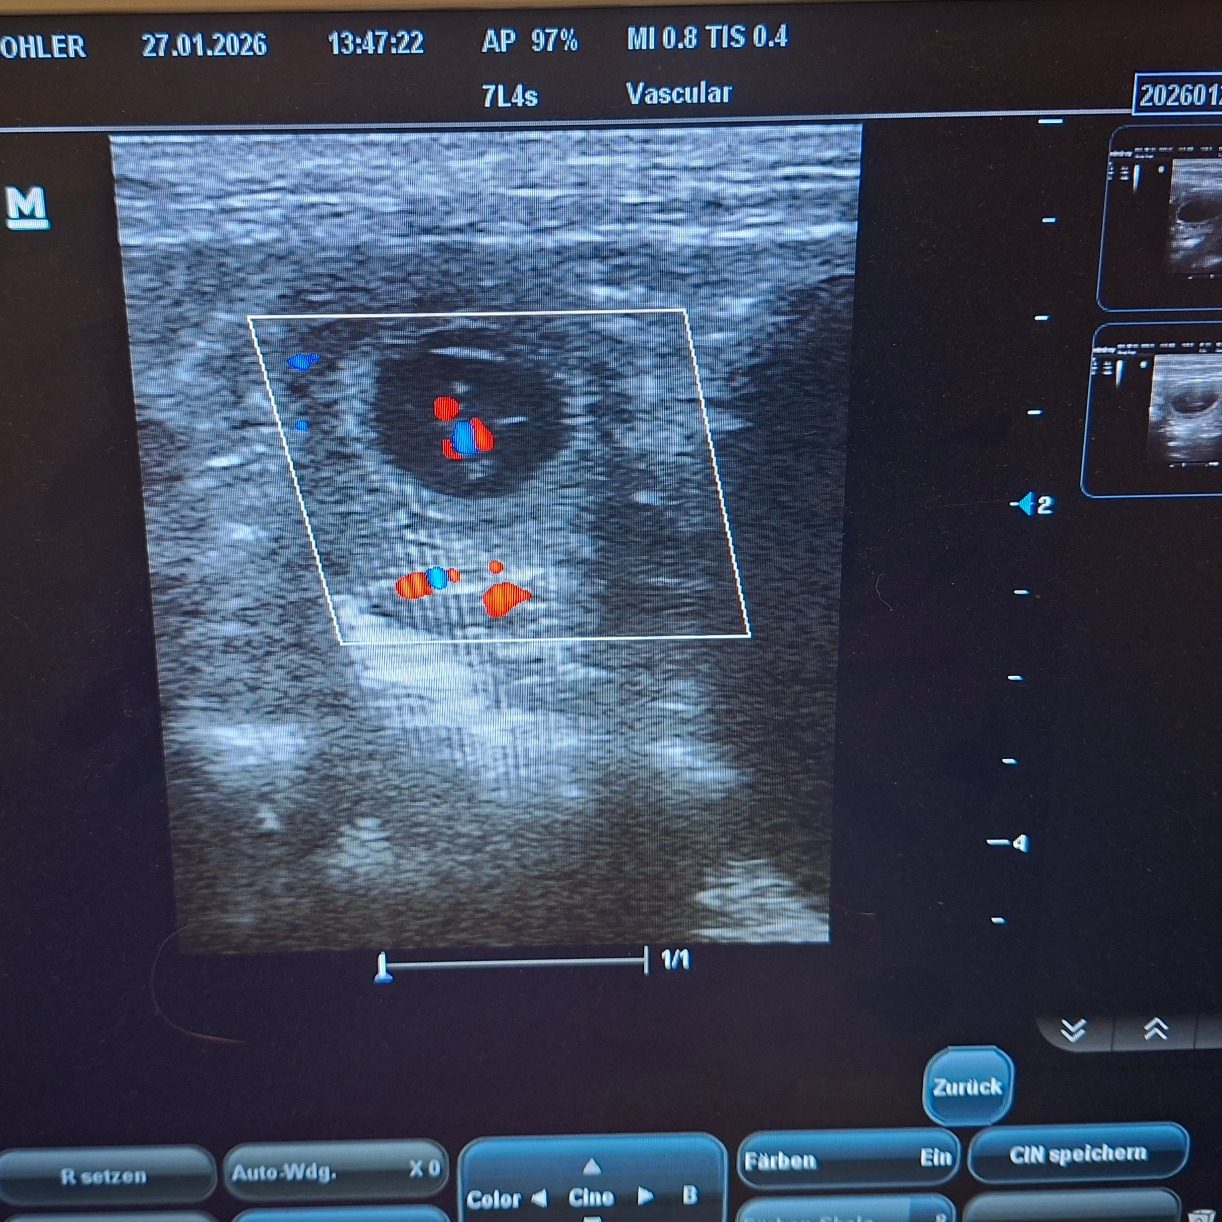

Endlich hatten wir den ersten Ultraschall und wir haben tolle Neuigkeiten

!!Kuba ist trächtig!!

Die letzten Tage waren für mich sehr sehr hart. Die Spannung war kaum auszuhalten. Ich wollte es jetzt endlich bestätigt haben, dass unsere Kuba trächtig ist. Ihr Verhalten und ihr Körper haben sich aber schon sehr verdächtig verändert. Sodass es heute eigentlich klar war, dass wir mit dem Ultraschall fündig werden. Wir haben nur einen kleinen Bereich geschallt und auch nicht lange, damit es für sie nicht zu anstrengend wird. Uns war nur wichtig zu sehen, dass es geklappt hat und die Kleinen leben. Alle Herzchen die wir gefunden haben schlugen ganz stark und alles sieht sehr gut aus.